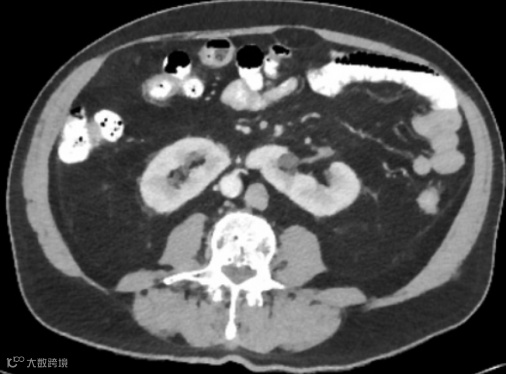

女,25岁,马蹄肾。肾脏下极相连,呈马蹄形,肾皮质厚度正常,泌尿系统未见梗阻扩张。

位置与融合:两肾下极(90%)或上极(10%)在中线处融合,形成峡部,峡部多位于腹主动脉前方。

旋转异常:肾门朝向前方或外侧,肾盂朝向前内侧,肾盏位于肾前方。

CTU能更清晰地显示旋转异常的肾盂肾盏和输尿管起始部。